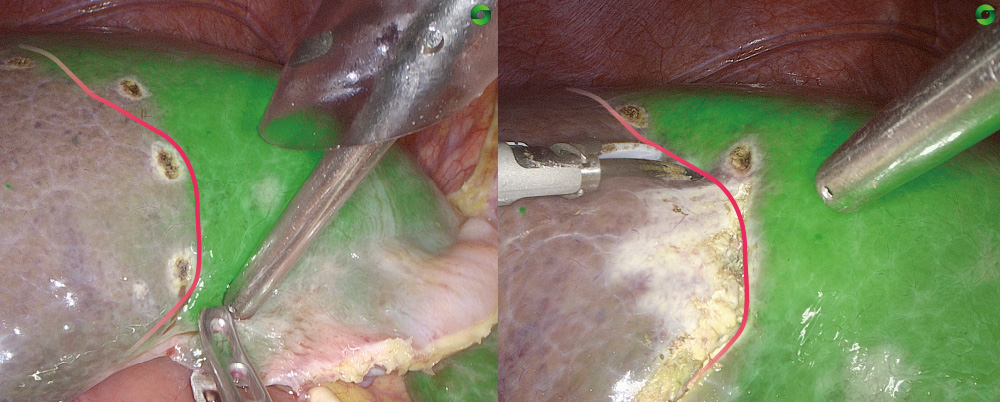

3D Fluorescence Imaging

Stable stereo fluorescence navigation makes surgical operations more precise.

Sensitive Perception, Precise Navigation

The Fluorescence Technology Significantly Boosts Detection Sensitivity and Fluorescence Imaging Stability, Leading to More Precise Navigation

Clinical Cases